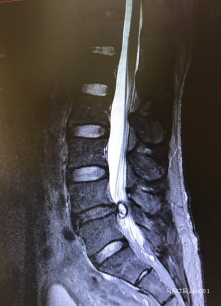

2.軟組織壓迫腰椎間盤突出症和腰椎管狹窄症引起馬尾神經受損 腰椎間盤突出症合併馬尾神經損傷的發生率為7%左右。曾報道根袖段神經根營養的75 %來自腦脊液,25%來自血供,因此腦脊液受阻時營養大部分喪失。馬尾神經水腫消退後周圍粘連形成,即便行椎板切除,突出物摘除減壓,一段時間內腦脊液循環仍不能建立,使得馬尾神經繼發性損傷繼續加重。

3.出血 MRI檢查時能發現硬膜囊壓跡和椎管內佔位,血管造影可發現該佔位為活動性出血,血腫壓迫馬尾神經。